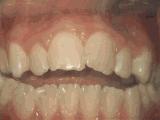

1、龅牙,前牙突出,个别牙齿扭转,通过专业评估,上下两侧各拔牙一颗后,经过矫正是变成这样的~